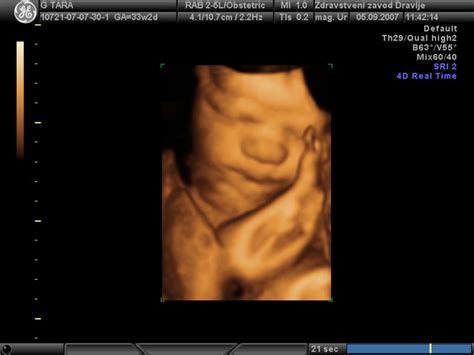

- Ultrazvočni pregled: UZ omogoča oceno stanja ploda, posteljice in dolžine materničnega vratu, kar lahko pomaga pri postavljanju diagnoze.